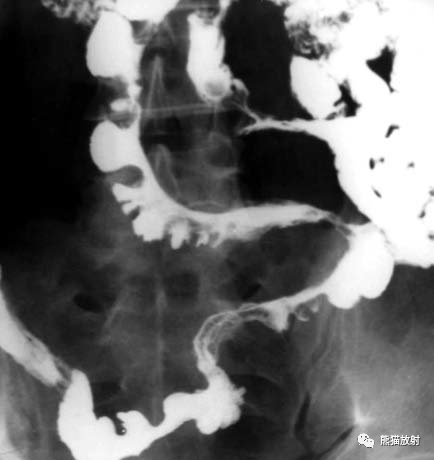

肠结核x线

肠结核x线,

增殖型:本型病变先侵犯盲肠,然后蔓延到升结肠和回肠末端,病变范围较